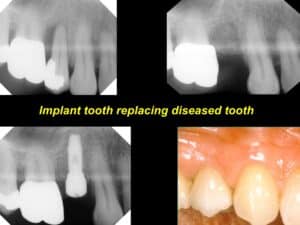

If you have suffered from periodontal disease, been subject to an injury, or if you have lost a tooth or several teeth due to some other reason, dental implants are an option for you. A dental implant is a fixture that is placed in your jaw and which imitates your tooth’s root. The implant then can to hold a new, replacement tooth or a bridge.